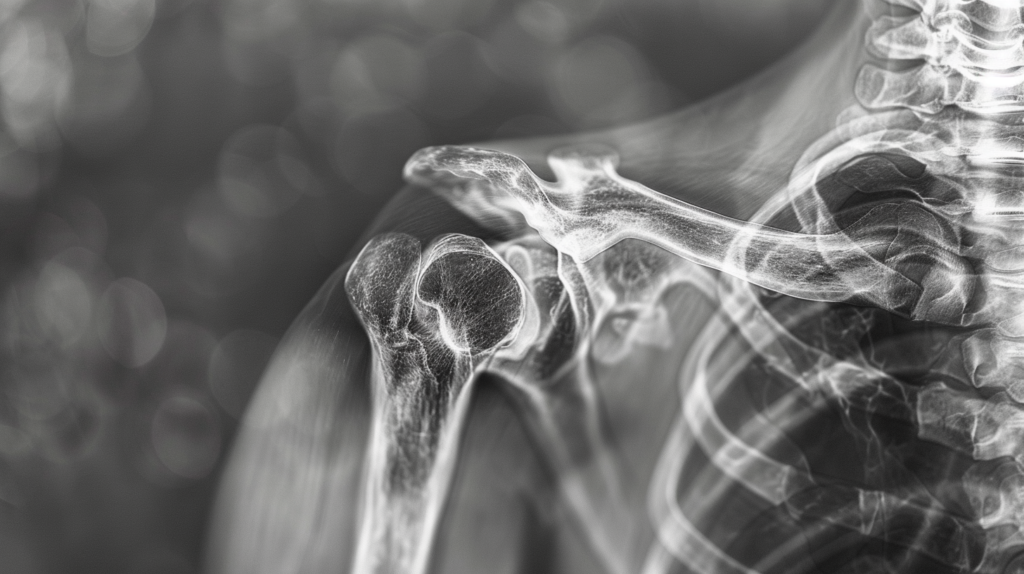

Чтобы понять, что такое артроз плечевого сустава, давайте сначала разберемся, как устроен здоровый сустав. Плечевой сустав – это сложная система, где головка плечевой кости входит в суставную впадину лопатки. Эти поверхности покрыты гладким хрящом, который обеспечивает плавное скольжение костей друг относительно друга. При артрозе этот хрящ начинает разрушаться.

Артроз плечевого сустава – это дегенеративное заболевание, при котором происходит постепенное разрушение хрящевой ткани сустава. Этот процесс может начаться незаметно, но со временем приводит к серьезным изменениям в структуре сустава. Кости начинают тереться друг о друга, вызывая воспаление, боль и ограничение подвижности.